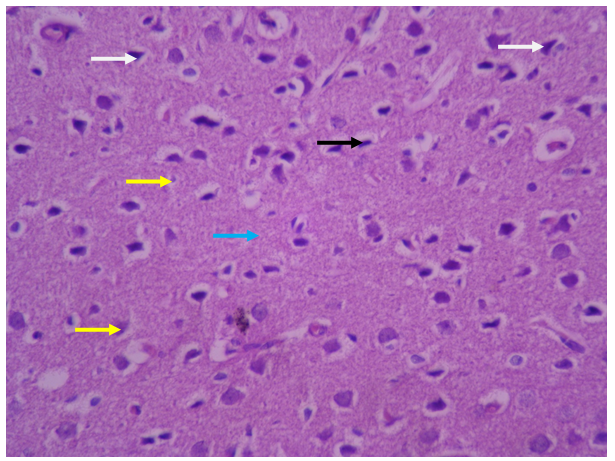

• Control

In the samples of the healthy control group, the brain tissue, gray matter and white layers are completely regular with healthy characteristics and normal cells visible (Figure 1).

Gray matter and its surface layer, called the molecular layer, have fewer cells and more nerve fibers, and its characteristics are quite normal. The various layers in gray matter zone are regular and with a normal number of cells. The characteristics of pyramidal neurons (white arrow) and neuroglycemic cells (yellow arrow) are completely normal and their nucleus and cytoplasm have a natural form and appearance. Microglia cells with dark and elongated nuclei are seen with appropriate dispersion and number (black arrow). Blood vessels and the structure of the blood-brain barrier (red arrow) are visible with a natural appearance. The neuropilezone is also seen with normal characteristics (blue arrow).

Figure 1. Photomicrograph of rat brain in healthy control group (Hematoxylin and Eosin staining×400)